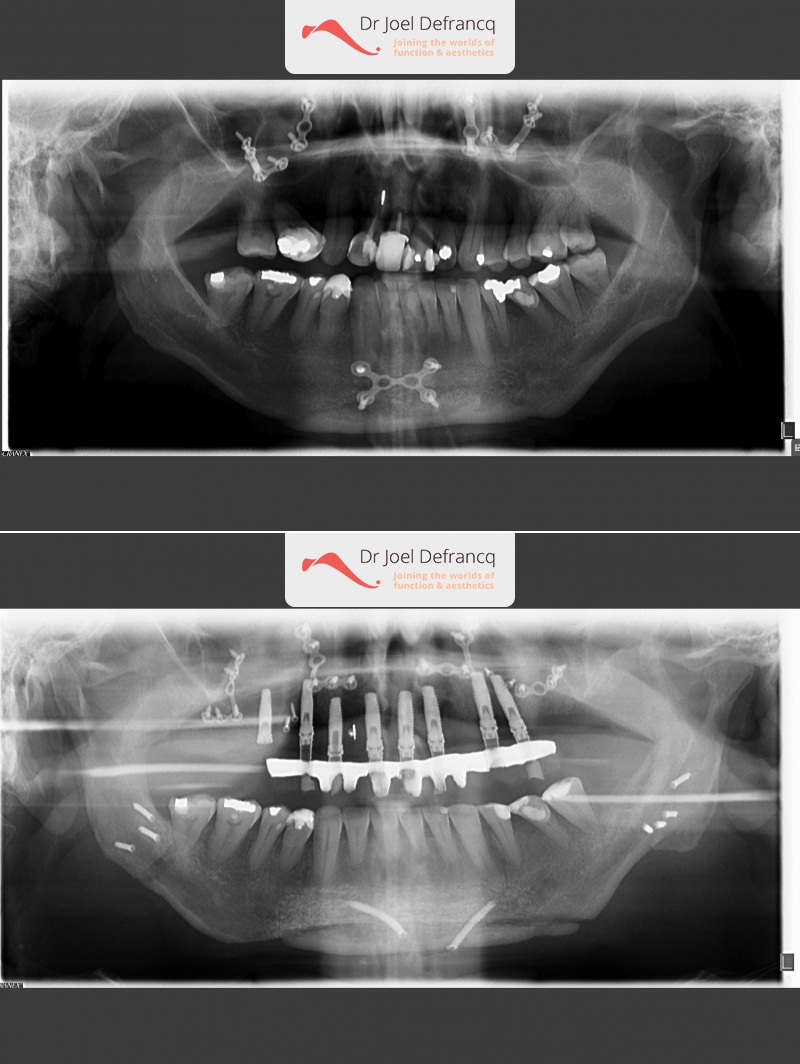

Jhonny: Kleine onderkaak, te kleine en te korte bovenkaak,

Kaakchirurgie

- Verlenging onderkaak (BSSO)

- Verlenging bovenkaak (Le Fort I)

- Kinchirurgie

- Verbreden bovenkaak (Smile distractor)

Behandeling tandheelkundige implantaten

- Vaste tanden op implantaten (bovenkaak)

- Implantaten met osteotomie

- Implantaten met beenopbouw